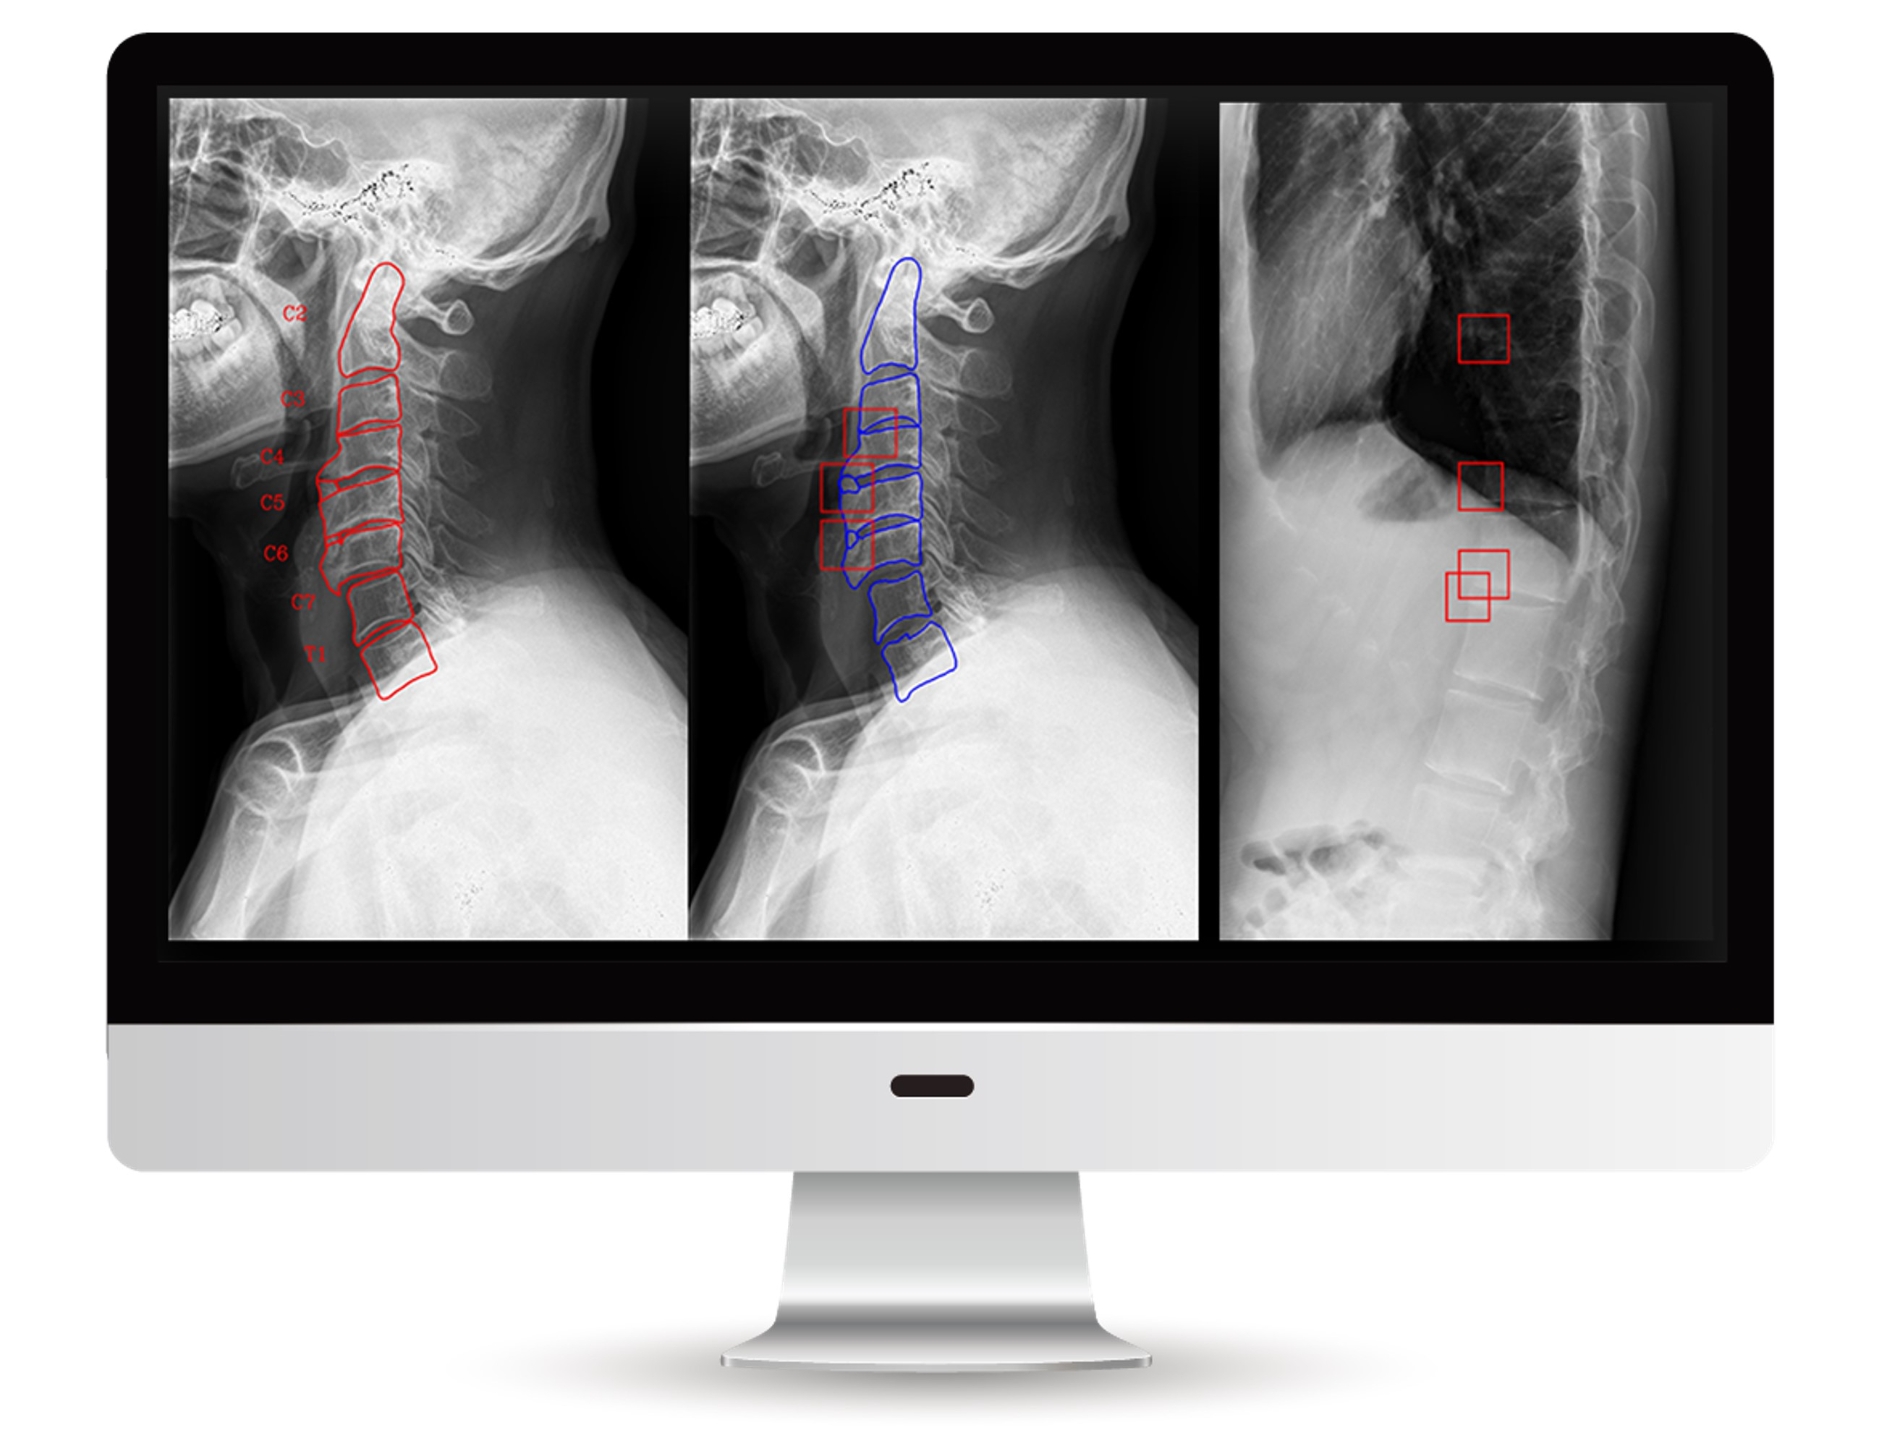

딥노이드 연구팀은 보라매병원 김동현 교수, 서울대학교 채희동 교수와 함께 2년여간의 공동연구및 임상 연구를 통해 척추 X-ray영상에 대해 인공지능 기반 강직성 척추염 자동 스코어링 알고리즘을 개발했다. 이러한 자동화를 통해 기존에 사람이 계산하는 방식보다 시간이 매우 단축되었으며, 이를 강직성 척추염 질환 평가에 사용한다면 진료의 효율화에 도움이 될 것으로 기대하고 있다. 딥노이드는 이번 연구결과와 추가 개발을 통해 식약처 인허가를 준비하고 있다.